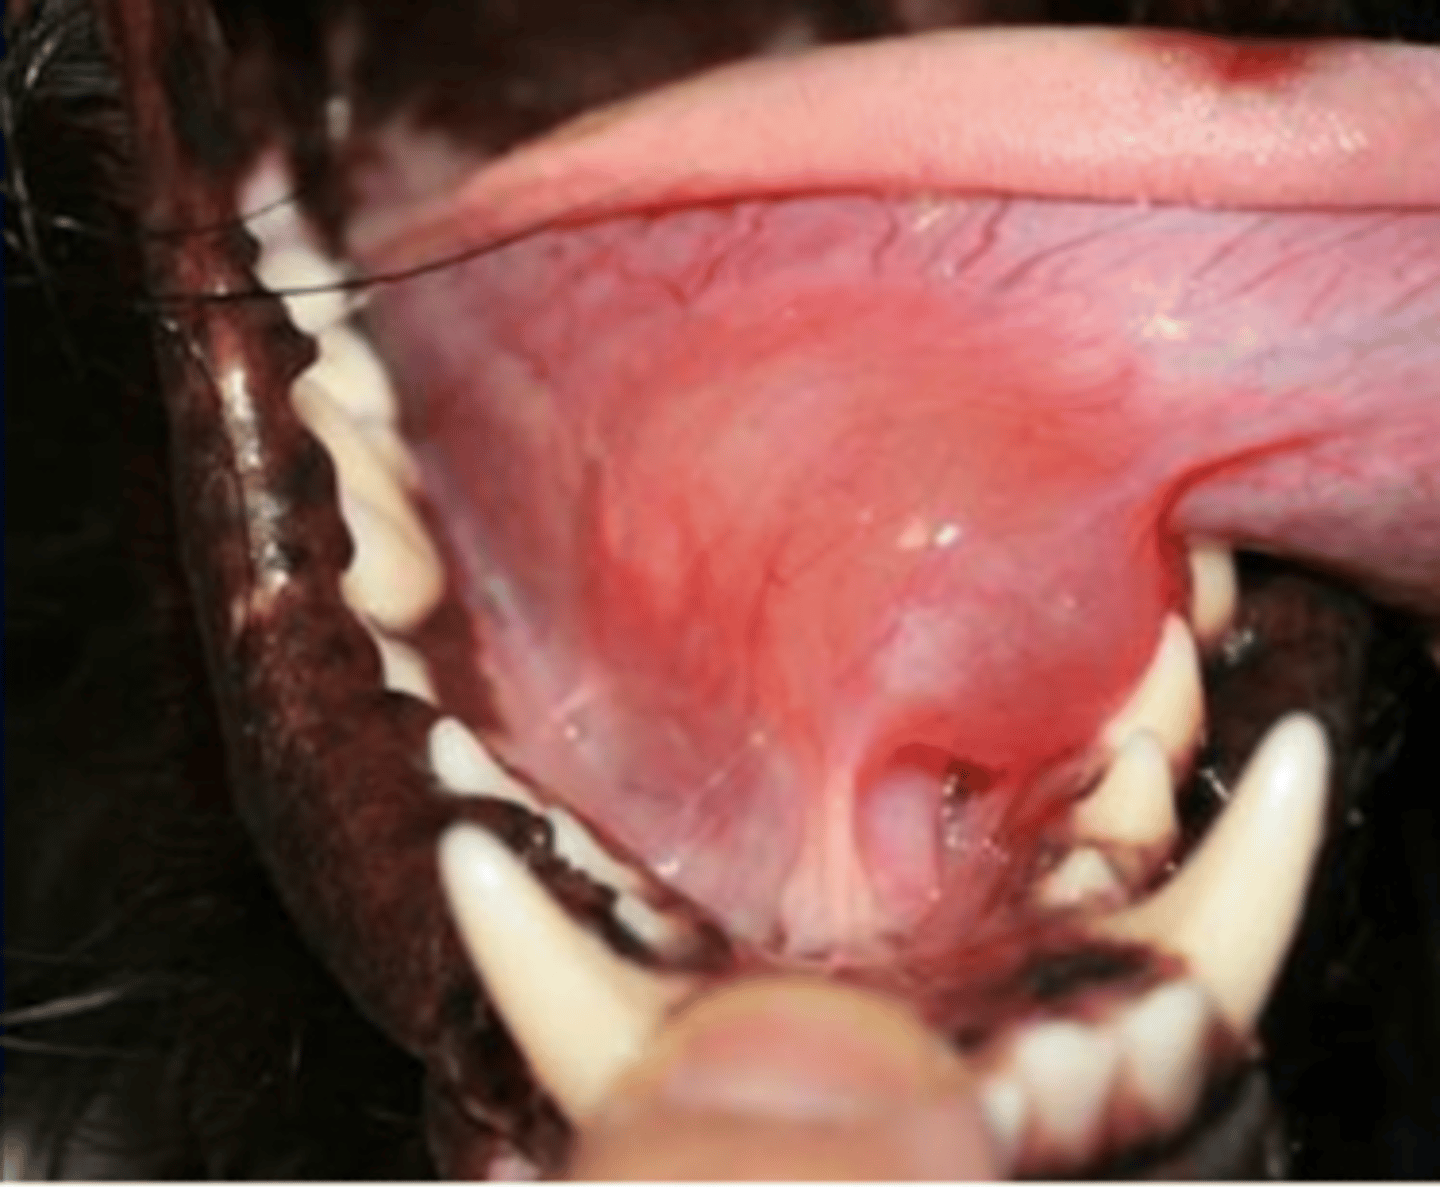

a mucocele/sialocele of the sublingual gland

what is a ranula?

prehension and mastication problems

if there is a mucocele/sialocele of the sublingual gland (ranula), what issues will we see in the dog?

a ranula (mucocele/sialocele of the sublingual salivary gland)

what is this?